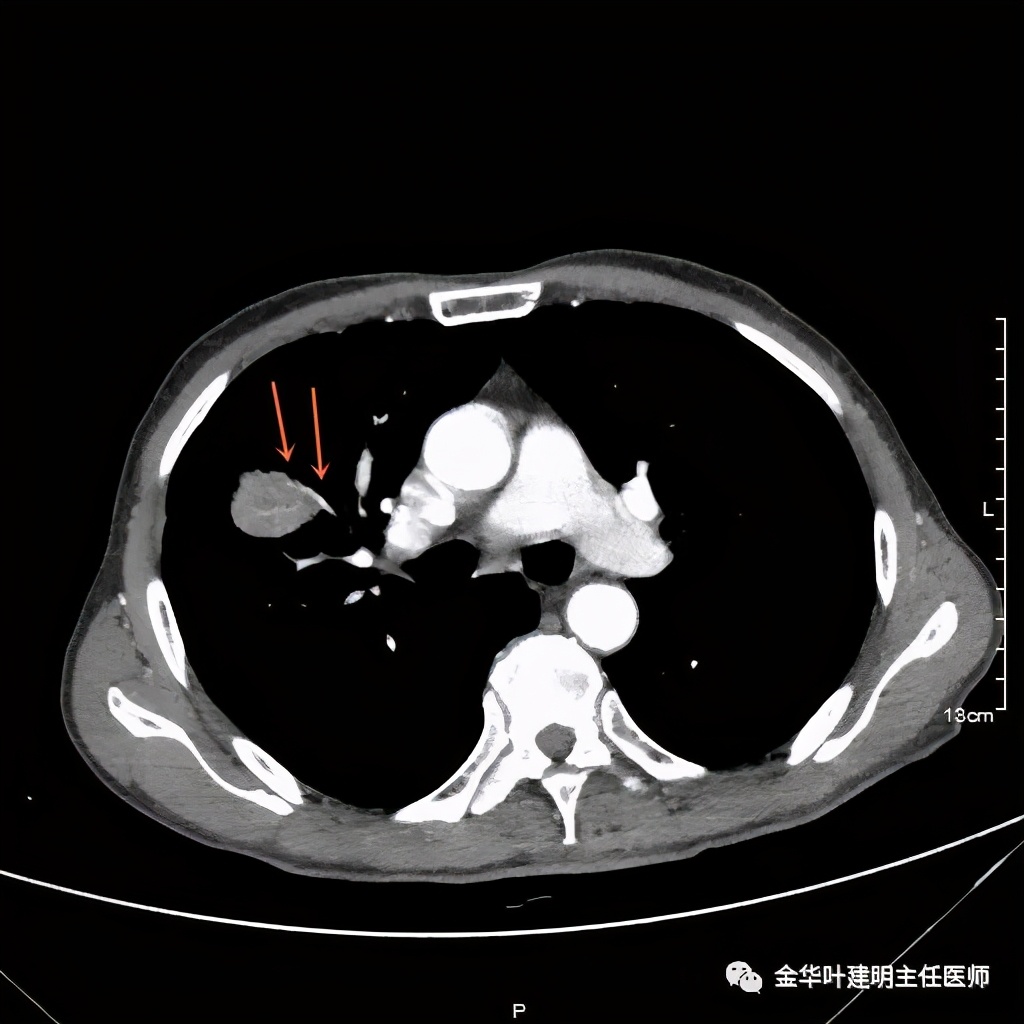

金华的某A,今年73岁,男性。检查发现右上肺占位,肿瘤筛查指标正常,血常规与CRP正常,临床有反复咳嗽、咳痰2年余(考虑慢支的关系,近期也许同时有病灶的影响)。一年前还在外院做过支气管镜,也未见确切异常。我们先来看他这次的胸部CT图像:

上图示病灶

上图桔色箭头示血管进入病灶,较粗;紫色箭头示病灶与胸膜间似乎有所牵拉;红色箭头示病灶

上图示纵隔窗实性